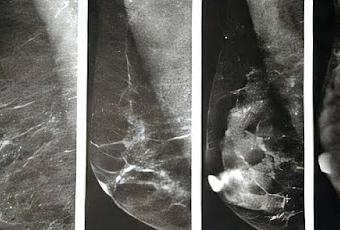

Las mamas contienen tres tipos principales de tejido: glandular, conectivo fibroso y graso. El tejido graso se ve oscuro en una mamografía, mientras que el tejido glandular y el conectivo fibroso se ven blancos. El problema es que los tumores también se ven blancos, lo que dificulta distinguir entre tejido mamario normal y cáncer.

Las mamas densas presentan mayor cantidad de tejido conectivo glandular y fibroso, y menor cantidad de tejido graso. La densidad mamaria se clasifica en cuatro categorías según el sistema BI-RADS del Colegio Americano de Radiología : Tejido mamario exclusivamente graso: Los senos están compuestos casi exclusivamente de tejido graso. Aproximadamente el 10 % de las mujeres presentan este tipo.

Tejido mamario fibroglandular disperso: Se presenta principalmente tejido graso con algunas zonas densas de tejido conectivo glandular y fibroso. Aproximadamente el 40 % de las mujeres presentan este tipo.

Tejido mamario heterogéneamente denso: Presenta numerosas áreas de tejido conectivo glandular y fibroso, con menos áreas de tejido graso. Aproximadamente el 40 % de las mujeres presentan este tipo.

Tejido mamario extremadamente denso: Tiene casi exclusivamente tejido conectivo glandular y fibroso. Aproximadamente el 10 % de las mujeres se encuentran en esta categoría y presentan un riesgo ligeramente mayor de cáncer de mama; se necesita más investigación para comprender por qué.

Se considera que las mujeres de los dos últimos grupos tienen "mamas densas".

Si su tejido mamario es exclusivamente graso o fibroglandular disperso, verá "no denso" en sus resultados. Si su tejido mamario es heterogéneo o extremadamente denso, verá "denso" en sus resultados.